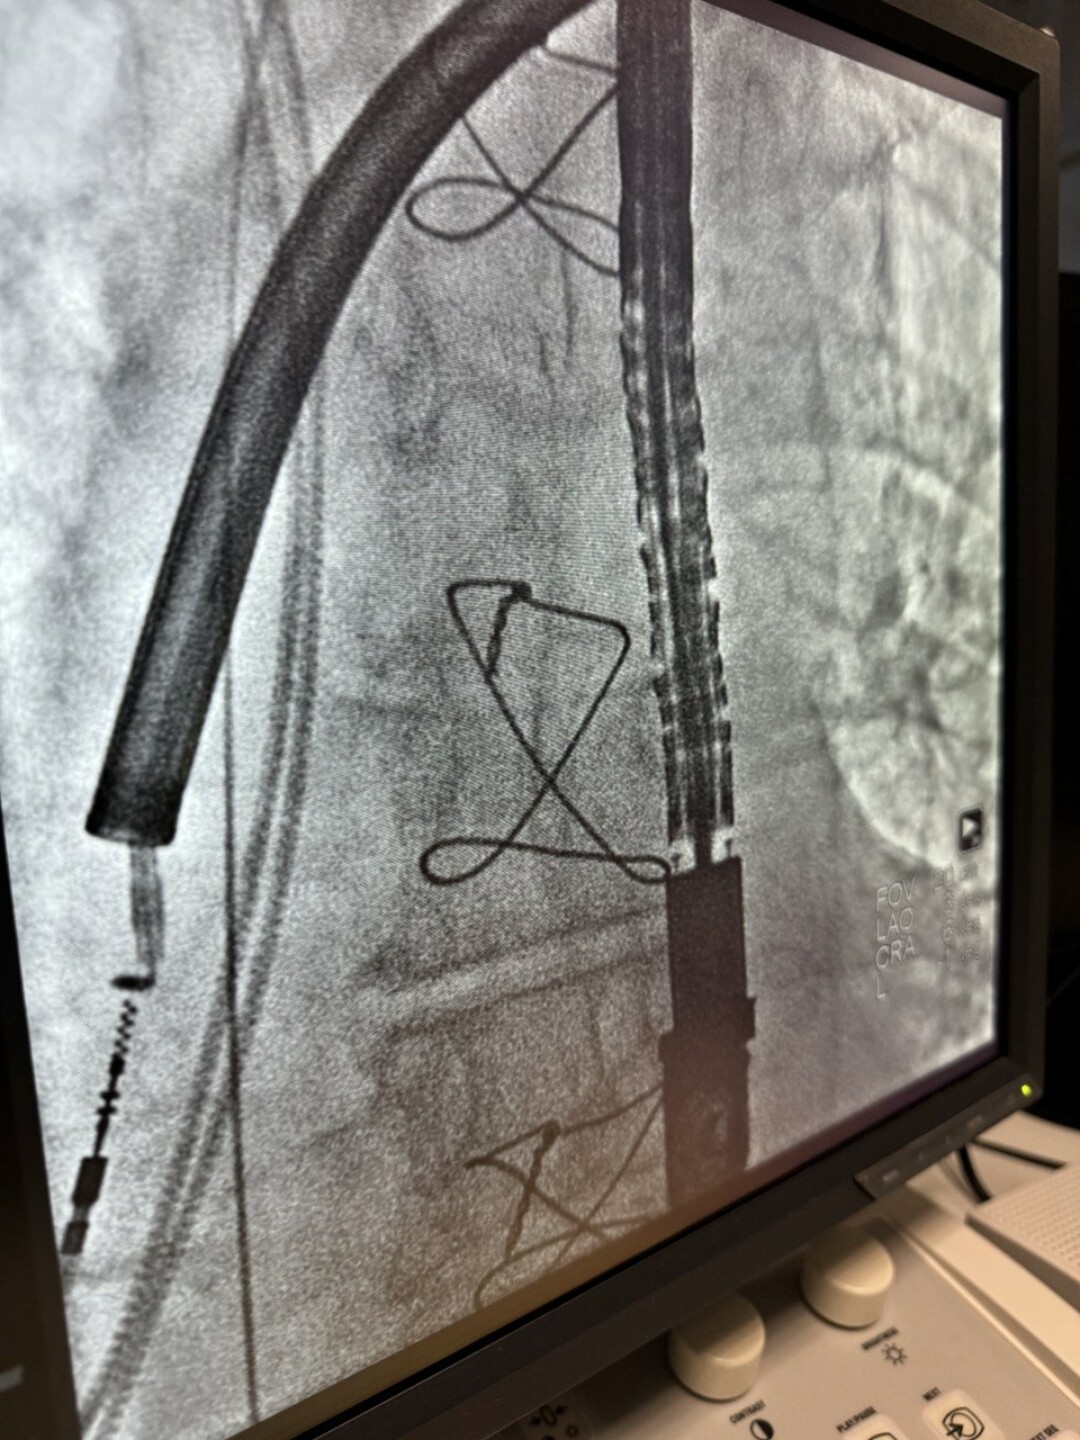

В Пермском крае провели первые операции по удалению электродов от кардиостимулятора

Впервые в Пермском крае прошла серия операций по удалению эндокардиальных электродов. Эту методику освоили и внедрили в Кардиоцентре. Для нее в режиме готовности находились все службы медучреждения — во время процедуры оперирующих врачей страховали кардиохирурги, анестезиологи-реаниматологи, трансфузиологи.

Трансвенозная экстракция считается сложной процедурой, так как электроды кардиостимулятора в течение 10-15 лет плотно обрастают рубцовой тканью, прочно крепятся к венам и сердечным структурам. «При замене водителя ритма сердца не всегда удается извлечь электроды, и они остаются в организме. Как любое инородное тело они могут стать причиной возникновения очага инфекции, что может привести к сепсису, и даже смерти пациента. При возникновении таких осложнений раньше выполнялись открытые кардиохирургические вмешательства с остановкой сердца», — объяснил заведующий отделением хирургического лечения сложных нарушений ритма сердца и электрокардиостимуляции Кардиодиспансера Владимир Щербенев.

В пресс-службе министерства здравоохранения рассказали, что механические экстракции помогают снизить риск повреждения вен и сердца во время операции. Это возможно благодаря более точному и контролируемому воздействию на электрод, но при такой процедуре особенно важны высокое мастерство и концентрация от хирурга. Этот способ выбрали извлечения старых электродов от электростимуляторов у двух мужчин, которых экстренно положили в больницу. Оба уже долгое время живут со стимуляторами, но электроды от предыдущих устройств оставались в сердце.

Впервые в Кардиодиспансере провели механическую экстракцию электродов при поддержке опытного сердечно-сосудистого хирурга из Нижнего Новгорода Сергея Айвазьяна, которому ассистировал пермский коллега Сергей Тимшин. «При извлечении высок риск повреждения тканей сердца и сосудов, кровотечений. Кроме того, надо было аккуратно обойти новые электроды, чтобы их не повредить. Именно поэтому условием проведения механической экстракции электродов является полная готовность всех служб клиники», — рассказал сердечно-сосудистый хирург Кардиодиспансера Сергей Тимшин.